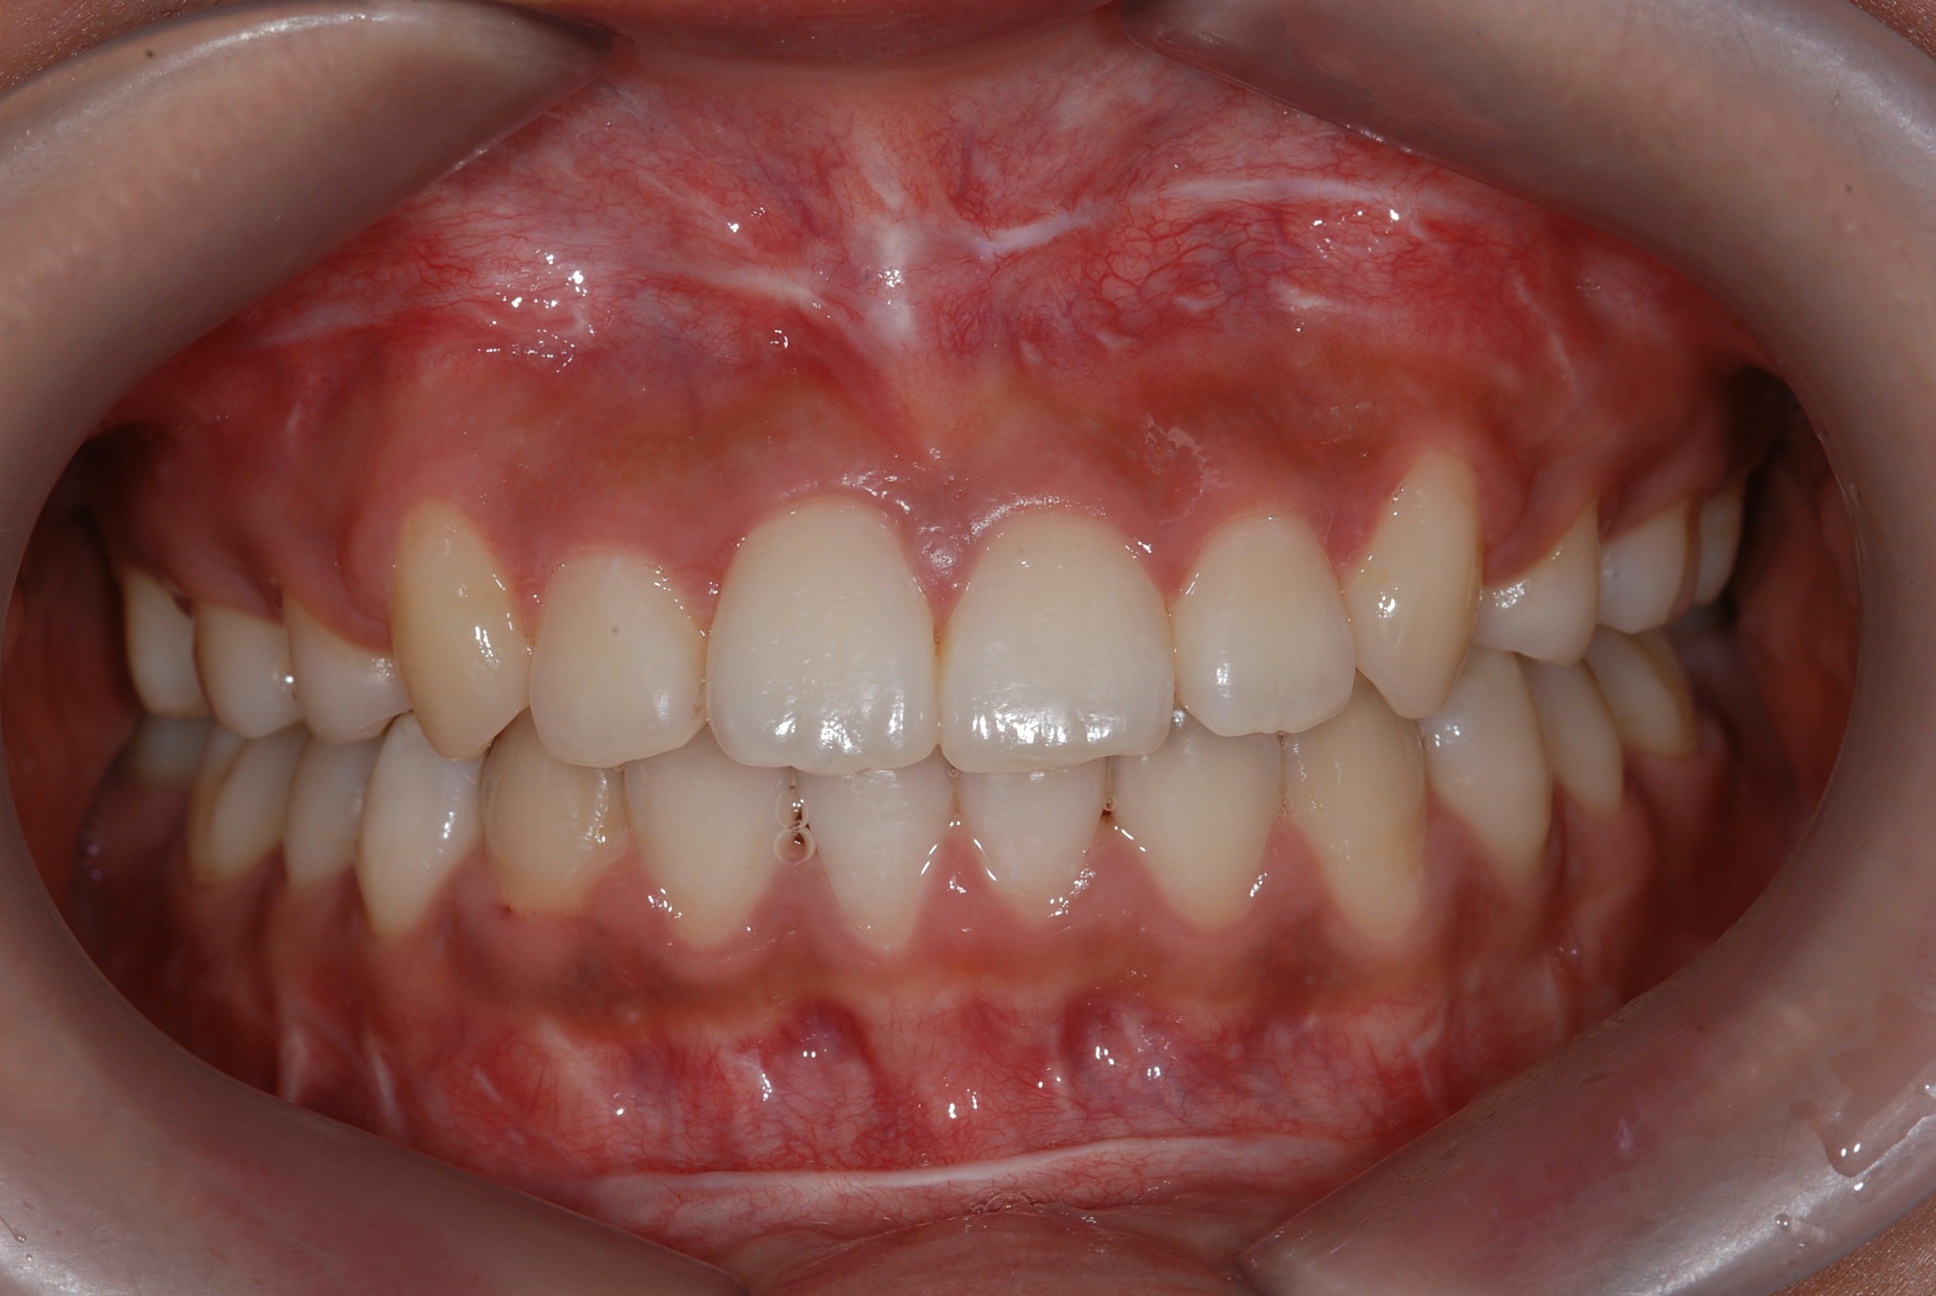

치료 후 사진입니다.